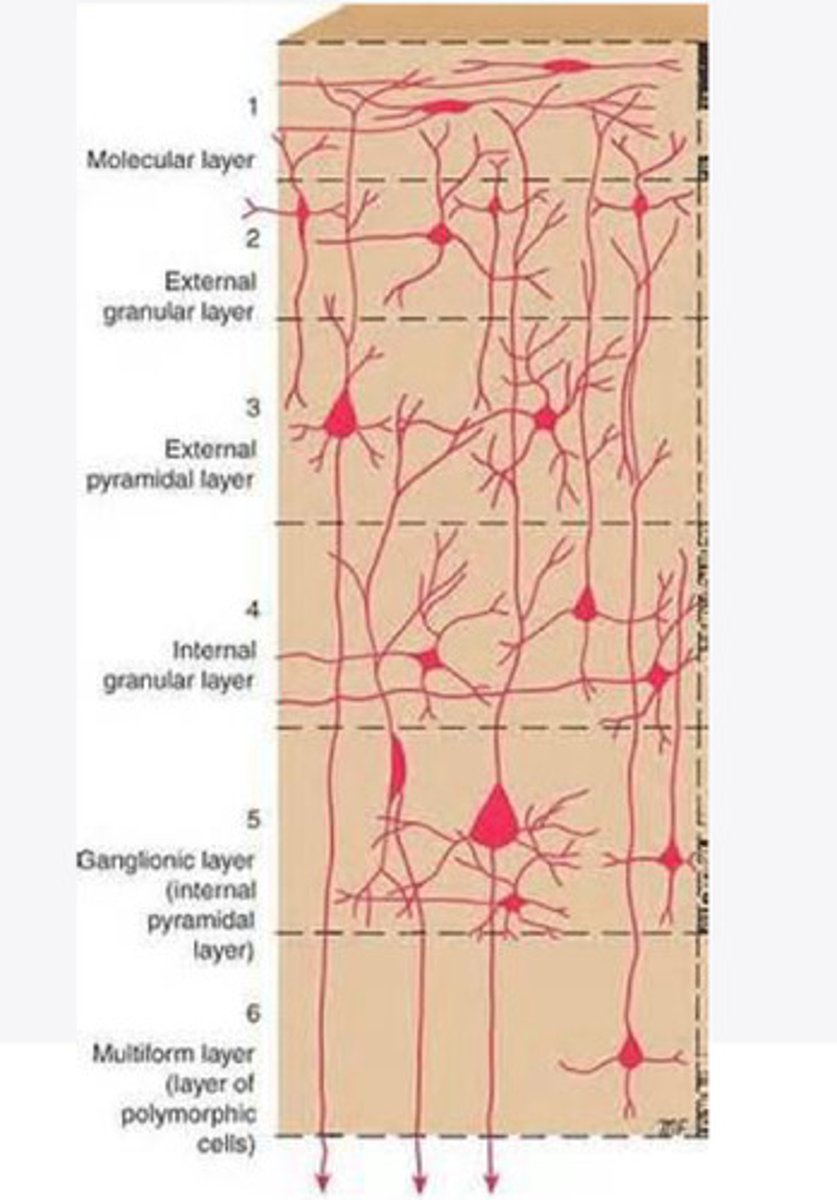

divided into 6 distinct layers, due to varying densities of cell body types within each layer

The cortex of the brain is divided into how many layers? Why is it divided into layers?

Layers of the cortex of the brain pic

2 and 4

What are the layers of the cortex that are associated with input?

3 and 5

What are the layers of the cortex that are associated with output?

molecular layer

What is the name of Layer 1 of the cortex of the brain?

very few cells

Does Layer 1 of the cortex have a lot or few cells?

receives dendrites from internal layers so it may actually function as a coordinating center where layers can communicate action

What does Layer 1 of the cortex do?

1

Every layer sends densities to Layer ____?

1

What layer serves as the "water cooler" of the brain?

external granular layer

What is the name for layer 2 of the cortex of the brain?

receives input from other cortical regions

What is the function of Layer 2 of the Cortex of the brain?

Stellate

What type of cells (stellate/pyramidal) would be most concentrated in Layer 2?

external pyramidal layer

What is the name for layer 3 of the cortex of the brain?

sends output to the other cortical layers

What is the function of Layer 3 of the cortex of the brain?

pyramidal

What type of cells (stellate/pyramidal) would be most concentrated in Layer 3 of the brain?

Layers 2 and 3

What layers are associated with association and commissural fibers?

Layer 3 - axons of cell bodies

Layer 2 - synapse into target areas in Layer 2

What part of the axons is in Layer 2/ in layer 3?

Layer 3 - external pyramidal layer

All axonal cel bodies for association and commissural fibers lie within what layer of the Cortex of the brain?

internal granular

** or called the striate cortex because it is so thick that you can see a line through this layer even in unstrained brain slides

What is the name for the 4th layer of the cortex of the brain?

receives input from the thalamus, geniculocortical layer, and other brainstem areas

What is the function for the 4th layer of the Cortex of the brain?

very thick within the vision, auditory, and somatosensory areas

Is Layer 4 thick or thin within SENSORY areas of the cortex?

Internal pyramidal

What is the name for Layer 5 of the cortex of the brain?

sends axons to the brainstem (corticobulbar) and spinal cord (corticospinal)

What is the function of Layer 5 of the cortex of the brain?

in motor areas of the cortex?

Where is layer 5 very thick in the brain?

the frontal lobe -- very motor heavy

What lobe of the brain will have a thick layer 5 of the cortex of the brain?

the multiform layer

What is the name of layer 6 of the cortex of the brain?

-sends axons back to the thalamus through corticogeniculate fibers

-modulates what information the thalamus sends to the cortex to control the strength of the signal received and modulate what you pay attention to

What is the function of layer 6 of the cortex of the brain?

no

Is layer 6 a motor layer?